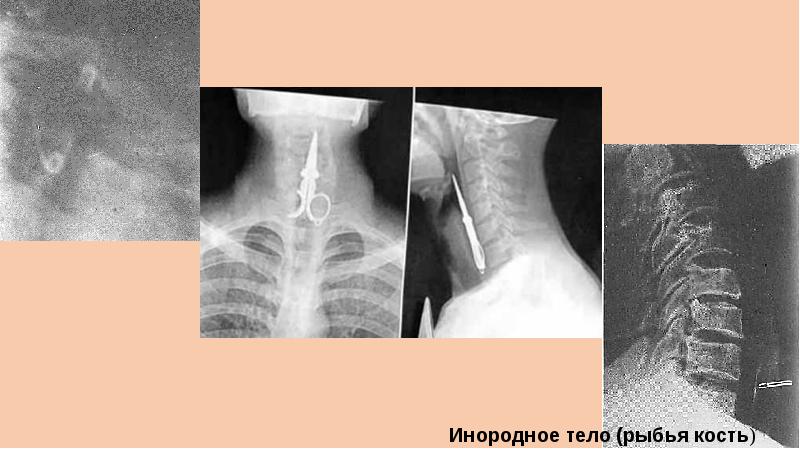

Инородное носа мкб 118 фото